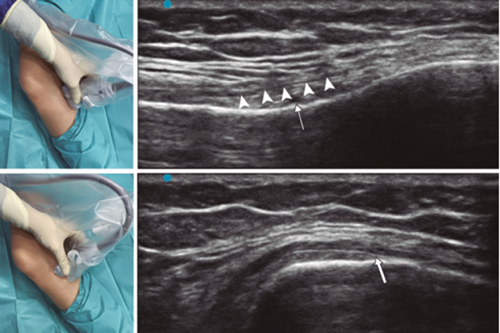

Figure 1

Figure 2

Figure 3

Figure 4